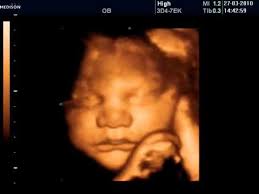

3D/4D Scan - Between 26 - 32 Weeks  (Incl Gender and the Growth of the baby)

R700

Between 26 and 32 Weeks

See your baby in 3D/4D using our state-of-the-art ultrasound machine. We will try our best to give you the most beautiful pictures of your unborn baby. We will also tell you the gender (if you want to know) at no extra cost.

This will be done in 3D/4D with images and a video. You will also receive a printed report. Please bring your own USB if you want the images and video immediately. We will be loading it onto our secure portal and send you a link to view and download it.